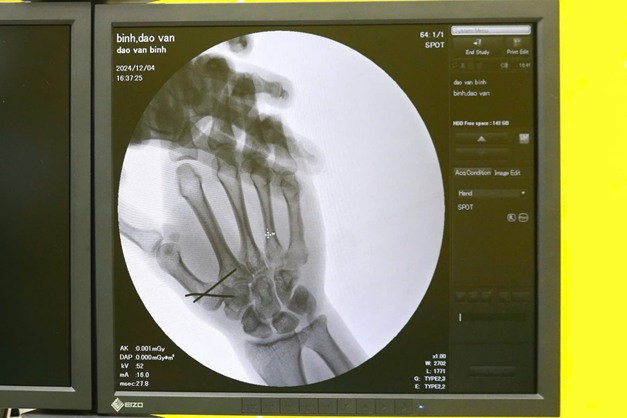

| Kết quả chụp X-quang cho thấy bệnh nhân bị gãy đốt 1 của ngón cái, mất vận động bàn tay - Ảnh BVCC, |

Kết quả chụp X-quang cho thấy anh bị gãy đốt 1 của ngón cái, mất vận động bàn tay, kèm nguy cơ di lệch thứ phát nếu không được can thiệp kịp thời. Đây là một tổn thương phức tạp, bởi ngón cái đóng vai trò quan trọng trong việc cầm nắm và thực hiện các chức năng chính của bàn tay.